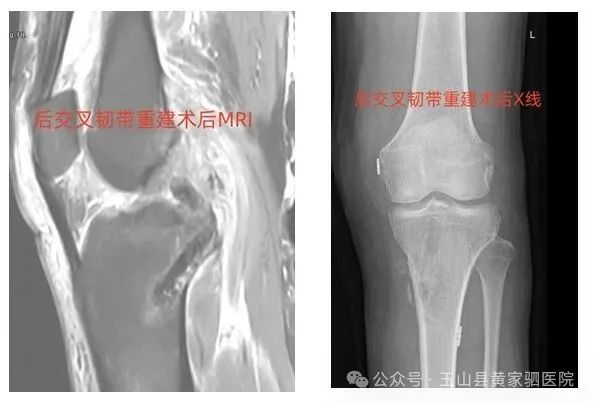

1.膝关节:膝关节前后交叉韧带重建、前后交叉韧带止点骨折镜下复位固定,内外侧副韧带微创重建,髌骨复发性脱位治疗、半月板成形、缝合术,关节清理术、关节镜下腘窝囊肿切除术等。